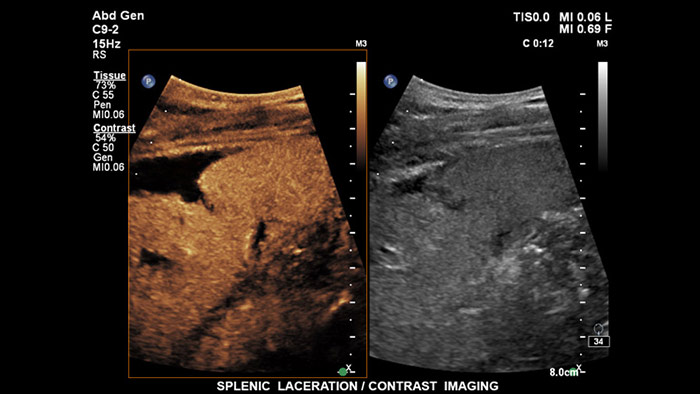

Ultrasonidos con contraste

Los agentes de contraste para ultrasonidos pueden transformar el papel que desempeñan los ultrasonidos hepáticos, pues permiten que el usuario estudie los patrones de mejora de las lesiones hepáticas sospechosas en tiempo real, lo que ofrece la posibilidad de realizar diagnósticos más fiables y rápidos. Con EPIQ de Philips, los CEUS se integran a la perfección en el flujo de trabajo normal y proporcionan un nivel de detalle excepcional en exploraciones de la fase arterial, portal y tardía.  Además, EPIQ ofrece el mayor nivel de fiabilidad posible para la detección y caracterización de lesiones, incluso en las exploraciones más difíciles; esto es posible gracias a tecnologías avanzadas al alcance de su mano, entre las que cabe mencionar las siguientes: pantalla MaxVue FHD, transductor PureWave C9-2, imágenes de fusión y cuantificación Q-App.

Los agentes de contraste para ultrasonidos pueden transformar el papel que desempeñan los ultrasonidos, pues permiten que los profesionales sanitarios estudien los patrones de mejora de las lesiones hepáticas en tiempo real, lo que ofrece la posibilidad de realizar diagnósticos más definitivos y rápidos. Con los ultrasonidos de Philips, los ultrasonidos con contraste se integran a la perfección en el flujo de trabajo normal y ofrecen un nivel de detalle excepcional.